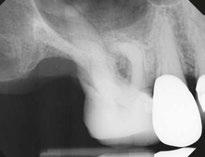

Let’s examine a case of a 58-year-old male who presented to my office in pain. He was referred as an emergency for consultation and treatment on either tooth No. 18 or 19. The patient presented with pain that had been on and off for over a month. The patient’s chief complaint was pain to cold and hot that lingered and now was spontaneous. On examination, tooth No. 19 responded to pulp testing within normal limits and was negative to percussion. Tooth No. 18 had a lingering sensitivity to cold, and a diagnosis of irreversible pulpitis and symptomatic apical periodontitis was made.

As you can see from final radiographs, the GentleWave Procedure’s ability to clean out and clear all portals of exit is on clear display here. I would not have had a similar outcome if I did not use the GentleWave Procedure.

Figure 1: Radiograph of tooth No. 18. The image on the right illustrates how the GentleWave Procedure cleans and clears all portals of exit